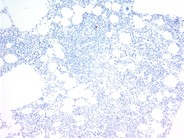

A bone marrow aspirate stained with Prussian blue showing marked iron overload in a patient with hereditary hemochromatosis and high serum ferritin level.